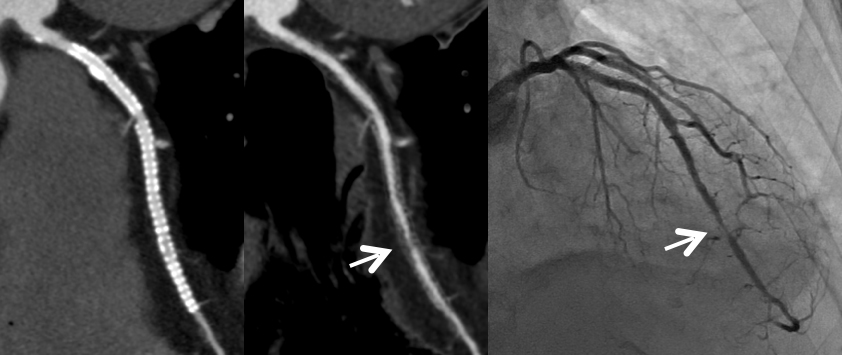

これまで、CTでは評価が難しいとされている冠動脈の強い石灰化部位やステント治療部位において、我々が考案した特殊な撮影(test bolus tracking法)および画像処理技術を用いて評価可能な画像を可能な限り提供しています。

通常の画像(左)ではSTENT内の評価は困難ですが、サブトラクション画像(中央)によって末梢側に高度狭窄を疑われます(矢印)。カテーテル造影(右)でも同様の位置に高度狭窄病変を認めます(矢印)。

Yamaguchi T. Ichikawa K, Takahashi D. et.al. A New Contrast Enhancement Protocol for Subtraction Coronary Computed Tomography Requiring a Short Breath-Holding Time. Academic Radiology Published online: October 17, 2016